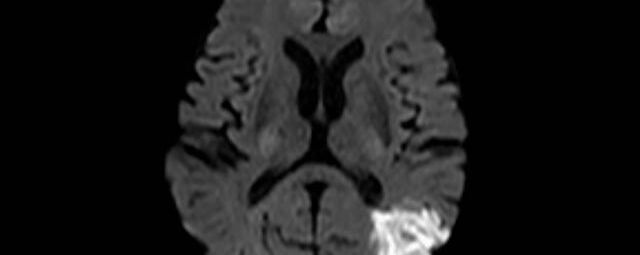

Kopf

• akute Schlaganfalldiagnostik und chronische Durchblutungsstörungen

• entzündliche Prozesse des Gehirns oder der Gesichtsweichteile

• Tumore, ggf. mit Spektroskopie

• Abklärung Schwindel, zentrale Sehstörung, Kopfschmerz

• Metastasenverdacht